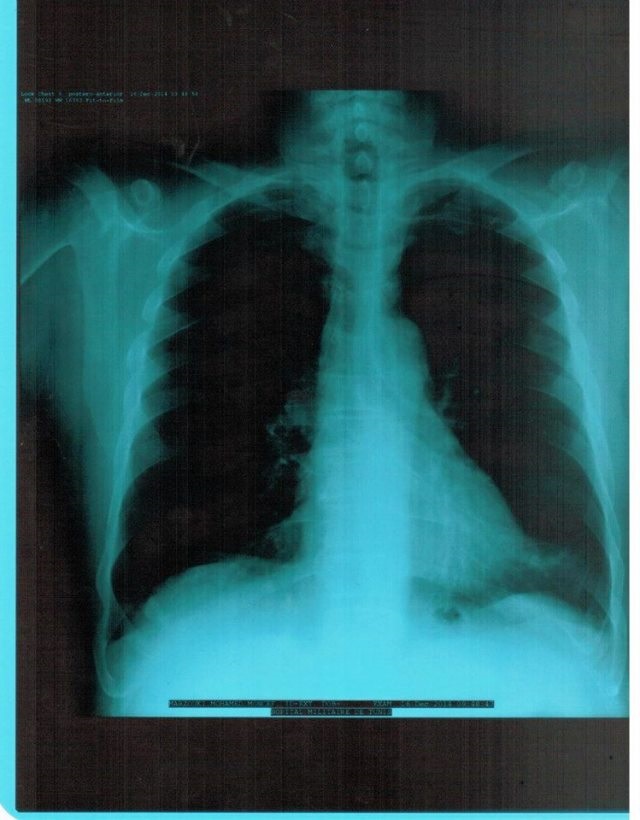

وجاءت هذه الحركة السبّاقة كاستجابة من المرزوقي لدعوات المطالبين بالكشوفات الطبية للمترشّحيْن.

وكان المنصف المرزوقي في وقت سابق قد نشر تصريحا على الشرف بجميع ممتلكاته استجابة أيضا لطلب الناشطين وبعض الأطراف السياسية، في خطوة سبّاقة وفريدة من نوعها، في حين لازال إلى حدّ الآن يرفض منافسه الباجي قائد السبسي نشر تصريحا لما يمتلك أو كشفا طبيا، رغم دعوات الكيرين، خاصّة بعد تردّد معلومات تفيد بإصابته بمرض يمنعه من أداء واجبه كرئيس للدولة.